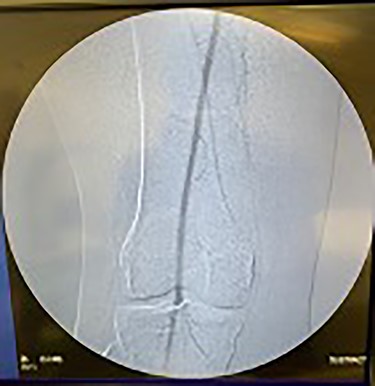

Catheter arteriogram results showed significant occlusion of the left iliac artery (Figs 3 and 4), the right iliac artery (Fig. 1), as well as the distal abdominal aorta (Fig. 2). There were numerous collateral vessels noted, indicating the presence of long-standing proximal stenosis (Fig. 1). The decision was made to use angioplasty to help widen the areas of stenosis. An 8 mm × 40 mm Passeo balloon was advanced from the right femoral artery into the left iliac artery (Fig. 7) and insufflated to 6 mmHg (Fig. 6). The balloon was allowed to remain expanded for 1 min and then was deflated. Next, the distal aorta was repaired in a similar fashion. The balloon was advanced into the distal aorta from the right femoral access and insufflated to 12 mmHg (Fig. 8). The balloon was allowed to remain expanded for 90 s.

Fluoroscopy of bilateral iliac arteries showing significant arterial disease.